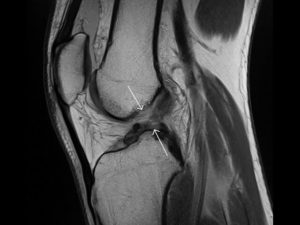

- МРТ. Также весьма эффективным методом является магнитно-резонансная томография. При её проведении используются электромагнитные волны, которые позволяют визуализировать не только плотные, но и мягкие материи. Благодаря этому можно отследить разновидность травмы.

Магнитно-резонансная томография позволяет увидеть все повреждения сустава, в том числе крестообразных связок, в 3d проекции.

- МРТ. Магнитно-резонансная томография является наиболее точной методикой подтверждения диагноза в отношении дегенерации связок колена с вероятностью до 95%;

- МРТ показывает в каком состоянии связки и тяжесть травмирования.